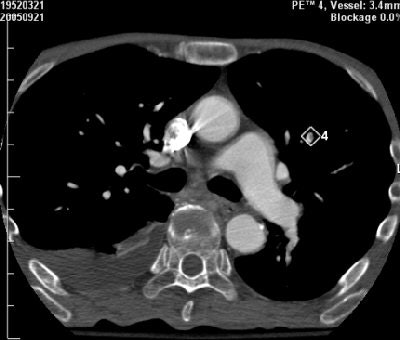

![]() |

| Above, false-negative PE finding, missed by CAD system and added manually by the radiologist. Below, perivascular soft tissue that produced a false-positive PE finding from CAD. Images courtesy of Dr. Zeev Maizlin and Dr. Peter Cooperberg. |